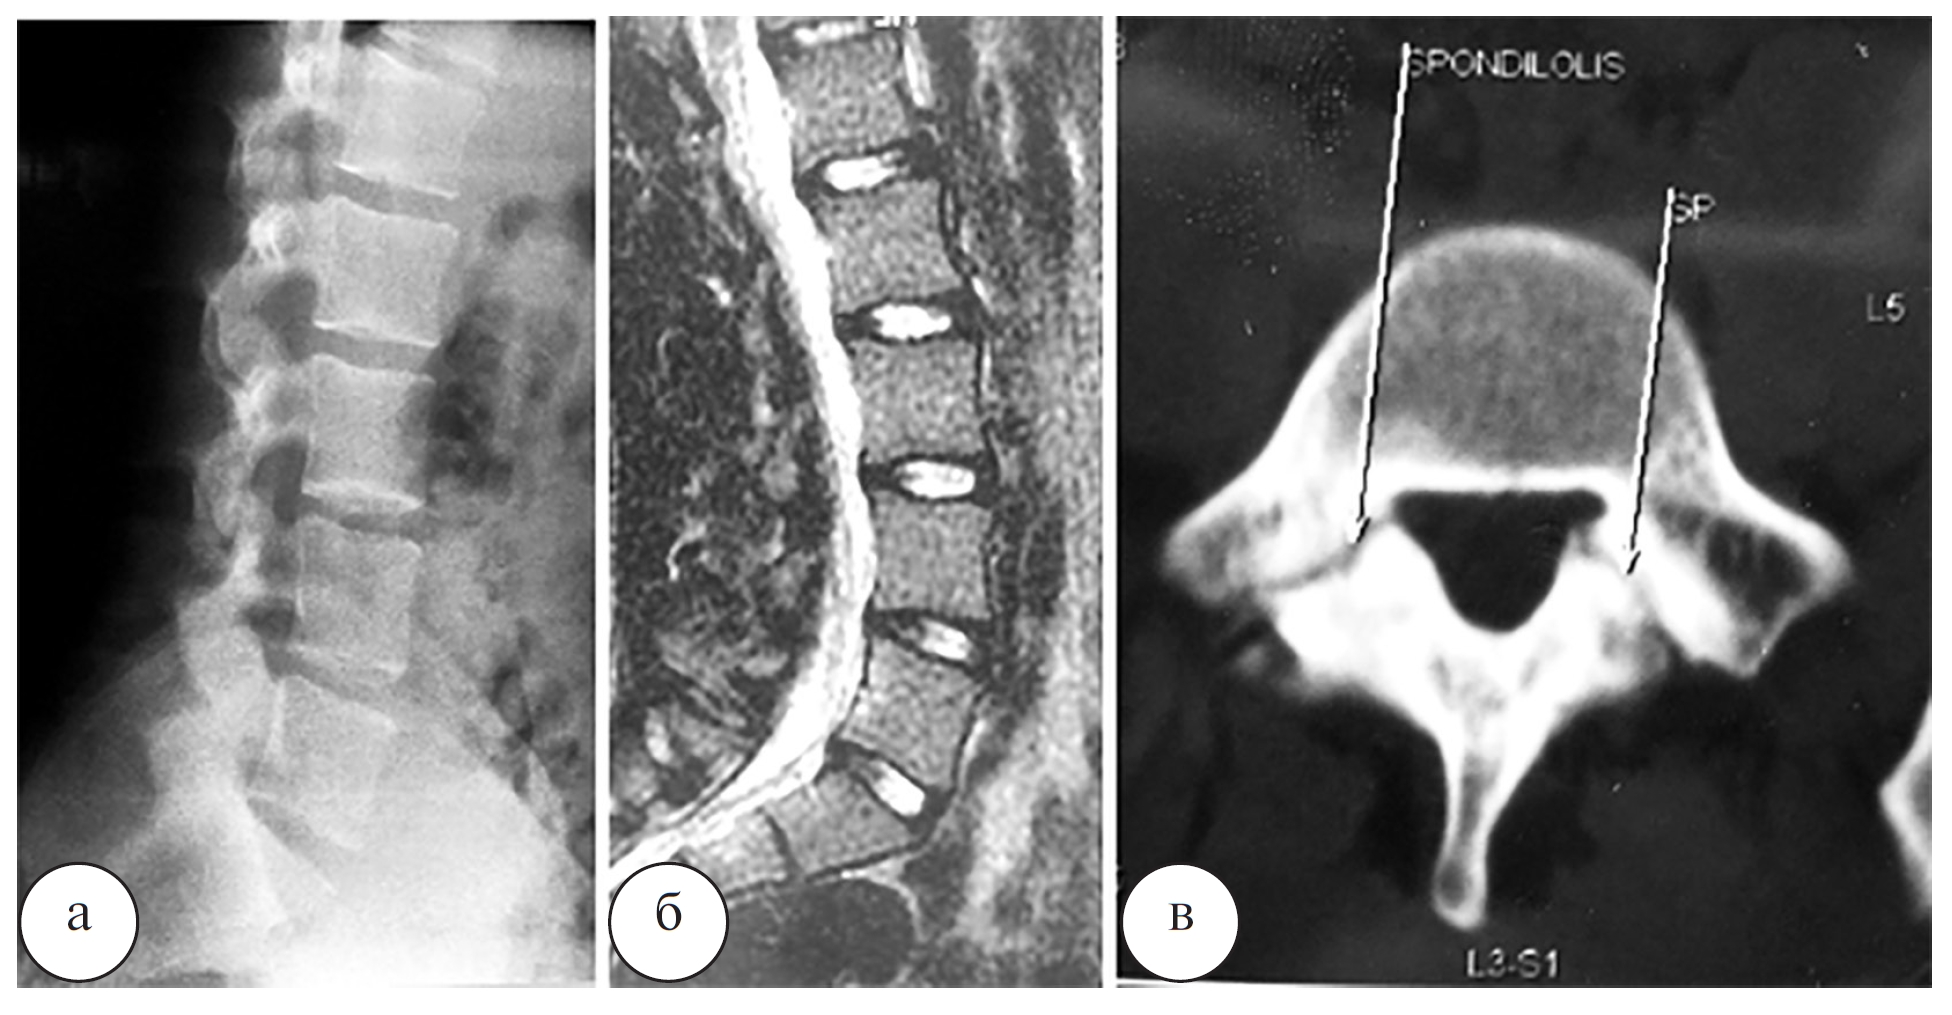

Длительность операции составила 200 мин, кровопотеря – 200 мл. При контрольных осмотрах было отмечено снижение интенсивности болевого синдрома в соответствии с визуальной аналоговой шкалой боли (visual analog scale – VAS) с 9 до 2, а также значений индекса Освестри (oswestry disability index – ODI) – с 65 до 10%. Начальные признаки сращения спондилолизных дефектов в зоне костной пластики по данным КТ были выявлены уже через 3 месяца после операции (рис. 8).

Рис. 8. Компьютерные томограммы L4 и L5 позвонков в аксиальной проекции (а – L4 позвонок, б – L5 позвонок) пациента Л. через 3 месяца после операции